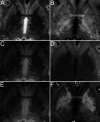

Post mortem magnetic resonance imaging (MRI) studies on the human brain are of great interest for the validation of in vivo MRI. It facilitates a link between functional and anatomical information available from MRI in vivo and neuroanatomical knowledge available from histology/immunocytochemistry. However, linking in vivo and post mortem MRI to microscopy techniques poses substantial challenges. Fixation artifacts and tissue deformation of extracted brains, as well as co registration of 2D histology to 3D MRI volumes complicate direct comparison between modalities. Moreover, post mortem brain tissue does not have the same physical properties as in vivo tissue, and therefore MRI approaches need to be adjusted accordingly. Here, we present a pipeline in which whole-brain human post mortem in situ MRI is combined with subsequent tissue processing of the whole human brain, providing a 3-dimensional reconstruction via blockface imaging. To this end, we adapted tissue processing procedures to allow both post mortem MRI and subsequent histological and immunocytochemical processing. For MRI, tissue was packed in a susceptibility matched solution, tailored to fit the dimensions of the MRI coil. Additionally, MRI sequence parameters were adjusted to accommodate T1 and T2∗ shortening, and scan time was extended, thereby benefiting the signal-to-noise-ratio that can be achieved using extensive averaging without motion artifacts. After MRI, the brain was extracted from the skull and subsequently cut while performing optimized blockface imaging, thereby allowing three-dimensional reconstructions. Tissues were processed for Nissl and silver staining, and co-registered with the blockface images. The combination of these techniques allows direct comparisons across modalities.